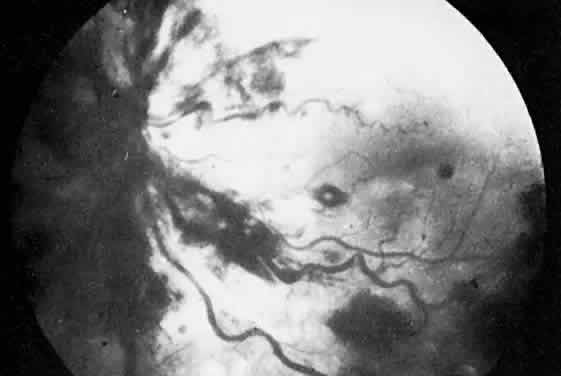

The most common ocular manifestations of TTP include papilledema, extraocular muscle palsies, and visual field defects, which usually are secondary to concomitant CNS involvement.75 Retinal findings consist of hemorrhages, retinal vascular occlusions, and serous detachments76,77 (Figs. 8 to 10). The cause of the serous detachments appears to be focal occlusion of the choriocapillaris resulting in retinal pigment epithelial damage and blood-retinal barrier disruption.76,77 Findings on fluorescein angiography are characterized by focal areas of nonperfusion of the choriocapillaris associated with late leakage into the subretinal space76 (Fig. 11). This is consistent with histopathologic studies that show occlusion of the choriocapillaris and large choroidal vessels, presumably by fibrin, with overlying necrosis of thepigment epithelium.75,76 TTP also has been linked in one case report with Purtscher retinopathy.78

Fig. 8. Patient with thrombotic thrombocytopenic purpura and extensive retinal vascular-occlusive disease. (Courtesy of William Mieler, MD.)

Fig. 9. Fluorescein angiogram of patient with thrombotic thrombocytopenic purpura and vascular-occlusive disease. (Courtesy of William Mieler, MD.)